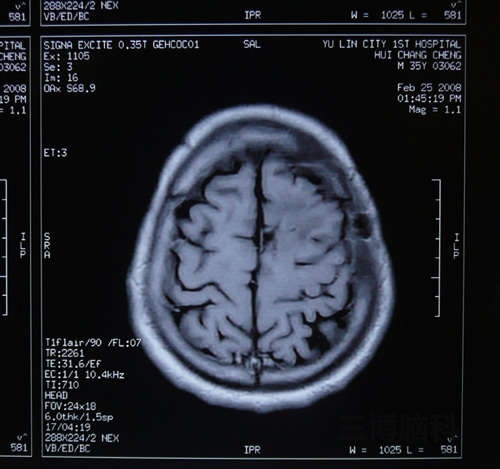

患者尹某,男,34岁。头痛、频发抽搐。MRI:左额顶近中先驱灶状占位,周围水肿明显。诊断:脑脓肿。立体定向微创技术切除病变。恢复良好。附图显示手术前后MRI比较。

术后显示:脑脓肿完全切除,患者症状消失,恢复良好。